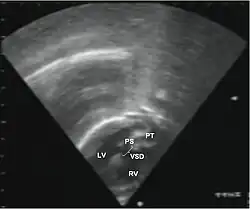

Echocardiography of a complex transposition with a ventricular septal defect and pulmonary stenosis.

Abbreviations: LV and RV=left and right ventricle, PT=pulmonary trunk, VSD=ventricular septal defect, PS=pulmonary stenosis.